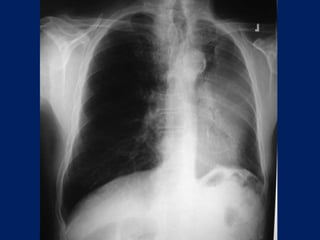

Chest radiographs may show the following:

• Pulmonary nodule, mass, or infiltrate

• Mediastinal widening

• Atelectasis

• Hilar enlargement

• Pleural effusion

Lung Cancer:

Findings on Chest X-ray

• Nodule (< 3cm) vs. Mass (>= 3cm).

– Location:

• Peripheral (Adenocarcinoma) vs.

• Central (Squamous).

– Single or multiple (metastases).

• Endobronchial obstruction.

– Atelectasis of lobe or lung.

– Pneumonia.